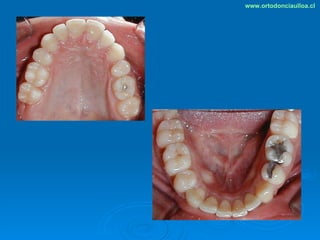

Este documento presenta dos casos clínicos de pacientes que recibieron tratamiento de ortodoncia. El primer caso fue de una paciente femenina de 14 años con apiñamiento dental y mordida cruzada que fue tratada mediante extracción de premolares y alineamiento dental. El segundo caso fue de un paciente masculino de 14 años con clase II esqueletal y desarmonía dentomaxilar que fue tratado con extracción de premolares y corrección de mordida. Ambos casos mostraron mejoría después de 3 años de tratamiento.